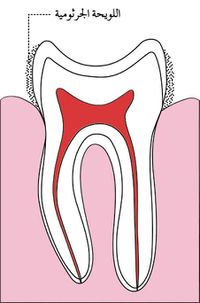

اللويجة الجرثومية

تتوضع على سطوح الأسنان طبقة عضوية رقيقة تدعى اللويحة الجرثومية bacterial plaque تتألف من طبقات كثيفة ومتراصة من الجراثيم ومنتجاتها والخلايا والبقايا الطعامية، وهي ذات طبيعة سكرية بروتينية لا تنحل باللعاب ولا تزول بغسلها بالماء بل تحتاج إلى فرشاة الأسنان لإزالتها.

بالإضافة لذلك فإن تجمع اللويحة الجرثومية Bacterial plaque في الميازيب و الوهاد السنية يزيد خطر الإصابة بالنخر. لذلك من المهم تغطية هذه الميازيب بمادة سادة.